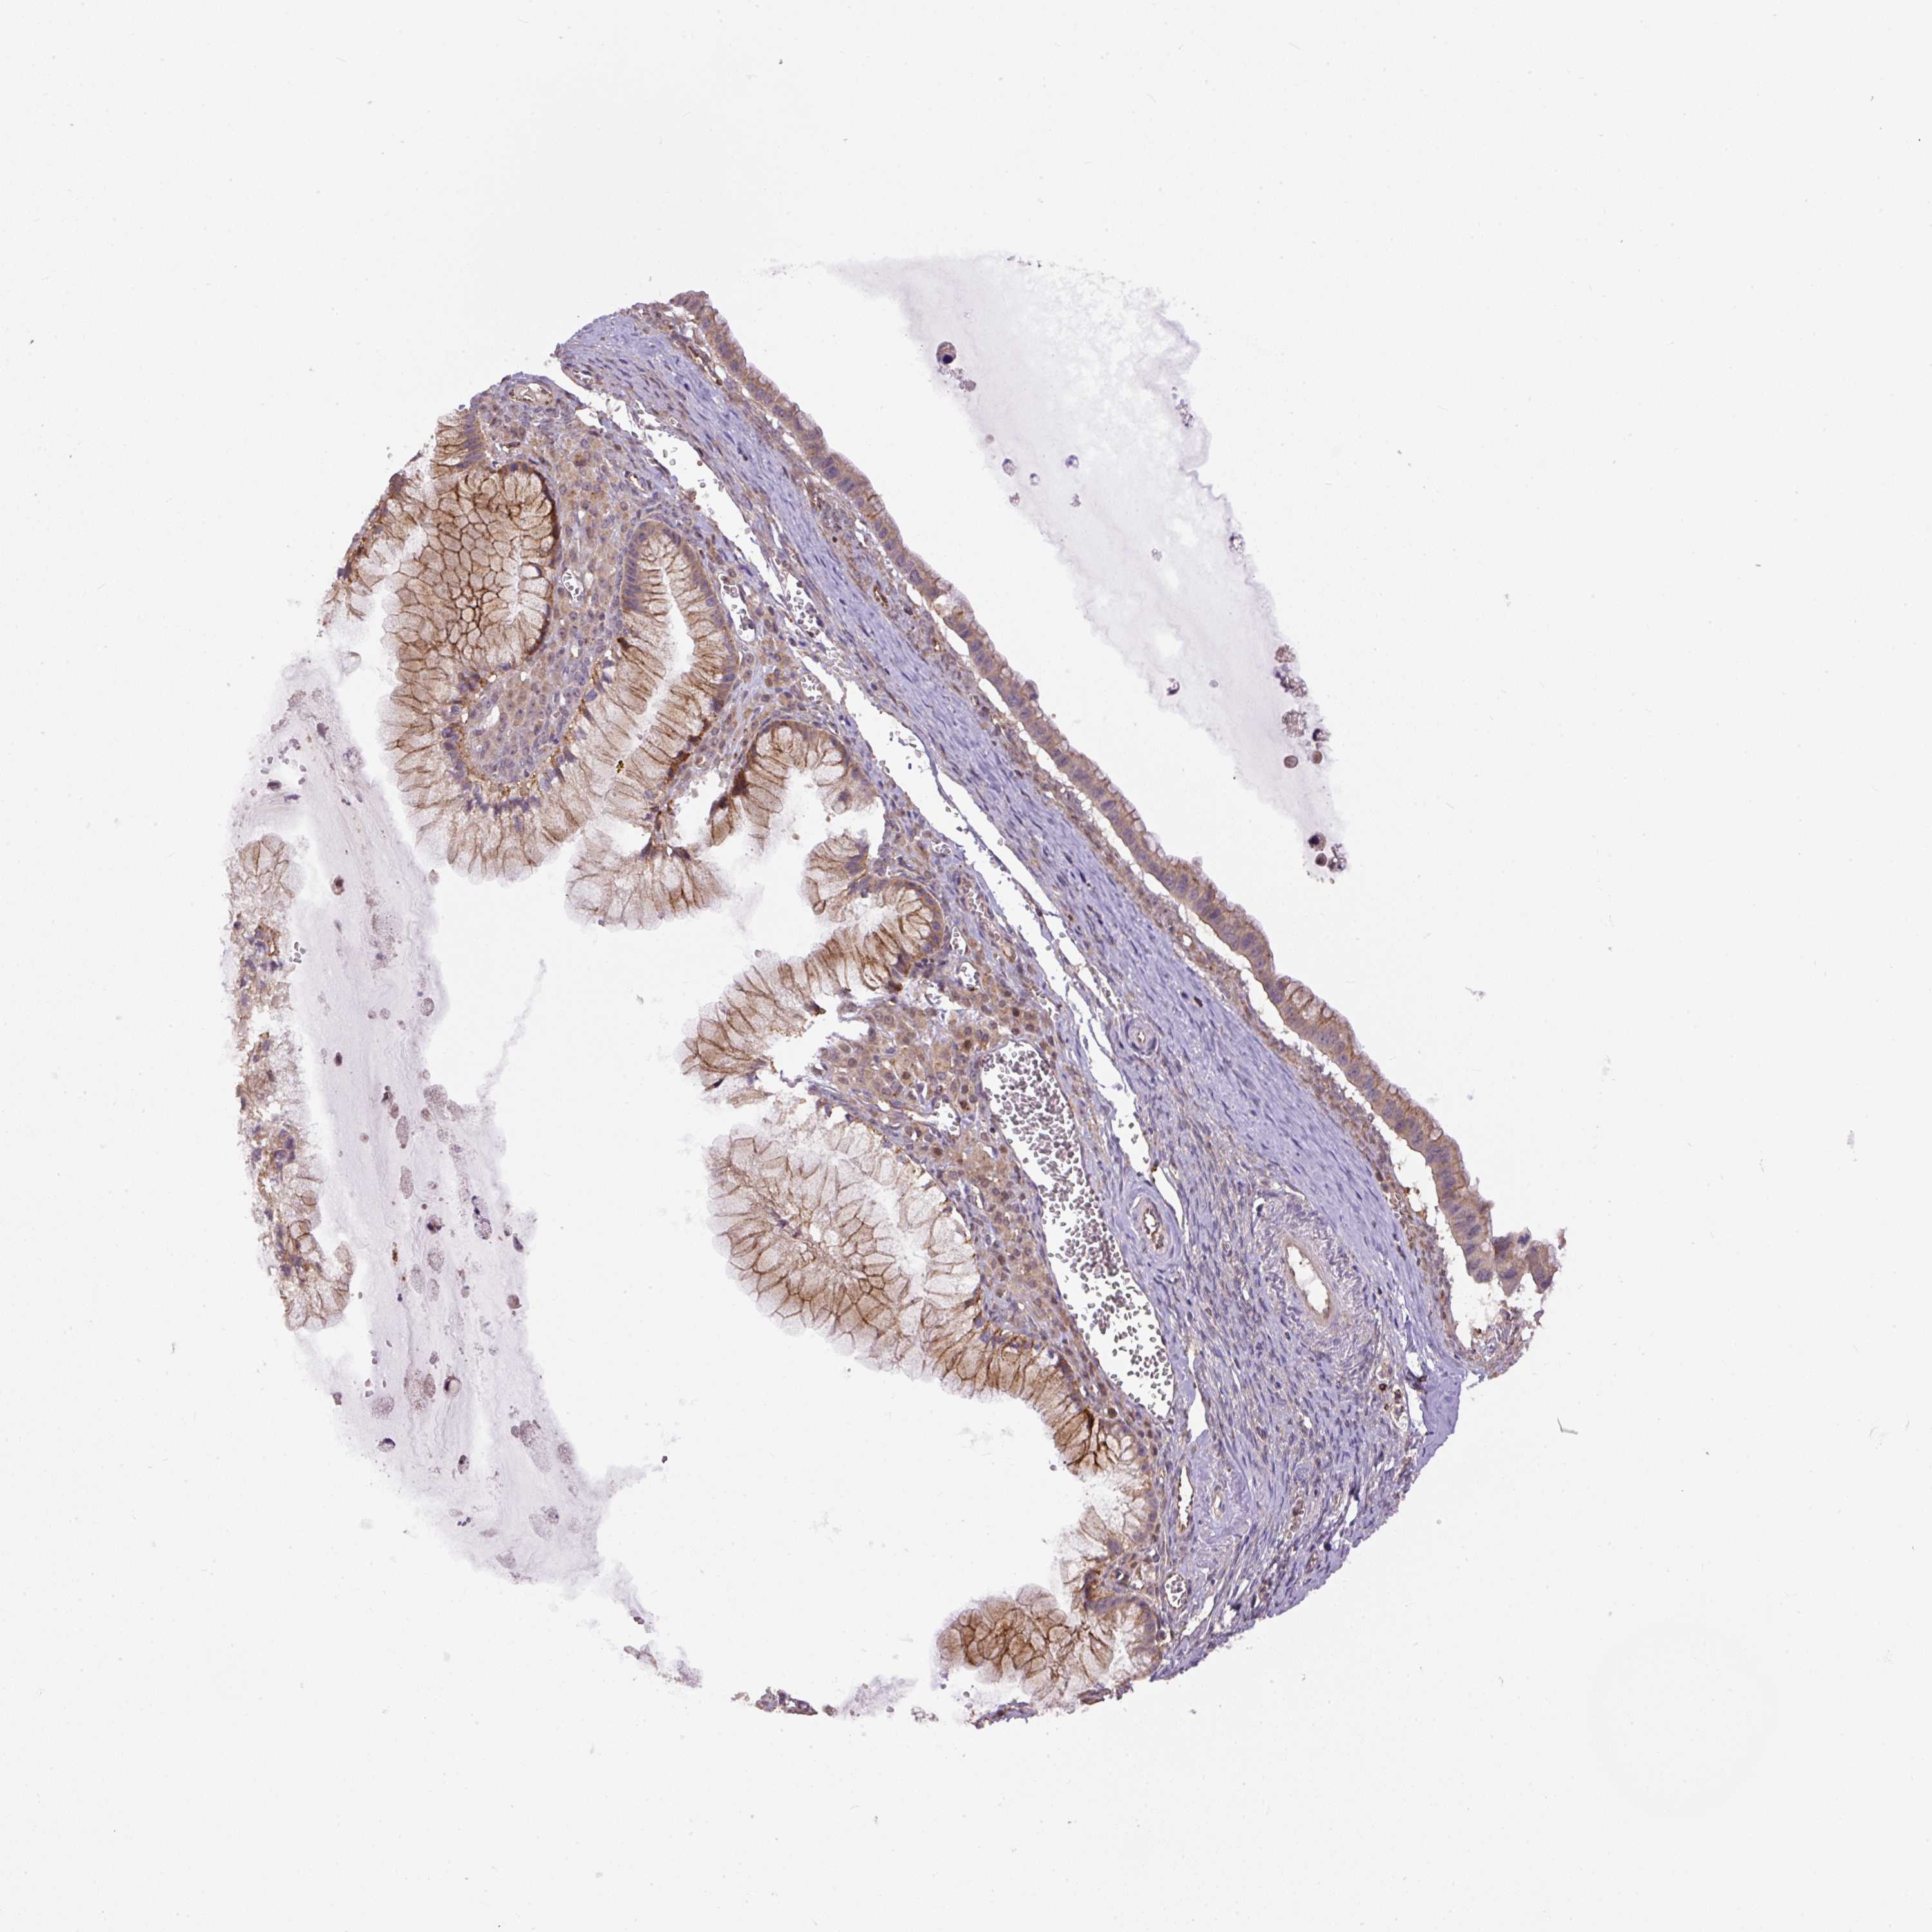

OVARIAN CANCER - Protein expressioni

A mouse-over function shows sample information and annotation data. Click on an image to view it in a full screen mode. Samples can be filtered based on level of antibody staining by selecting one or several of the following categories: high, medium, low and not detected. The assay and annotation is described here.

Note that samples used for immunohistochemistry by the Human Protein Atlas do not correspond to samples in the TCGA dataset.

Antibody stainingi

Antibody staining in the annotated cell types in the current human tissue is reported as not detected, low, medium, or high, based on conventional immunohistochemistry profiling in selected tissues. This score is based on the combination of the staining intensity and fraction of stained cells.

Each image is clickable and will lead to virtual microscopy that enables deeper exploration of all samples and also displays staining intensity scores, fraction scores and subcellular localization as well as patient and tissue information for each sample.

Antibody HPA043900

Antibody CAB004541

Cystadenocarcinoma, serous, NOS

Cystadenocarcinoma, mucinous, NOS

Carcinoma, endometroid